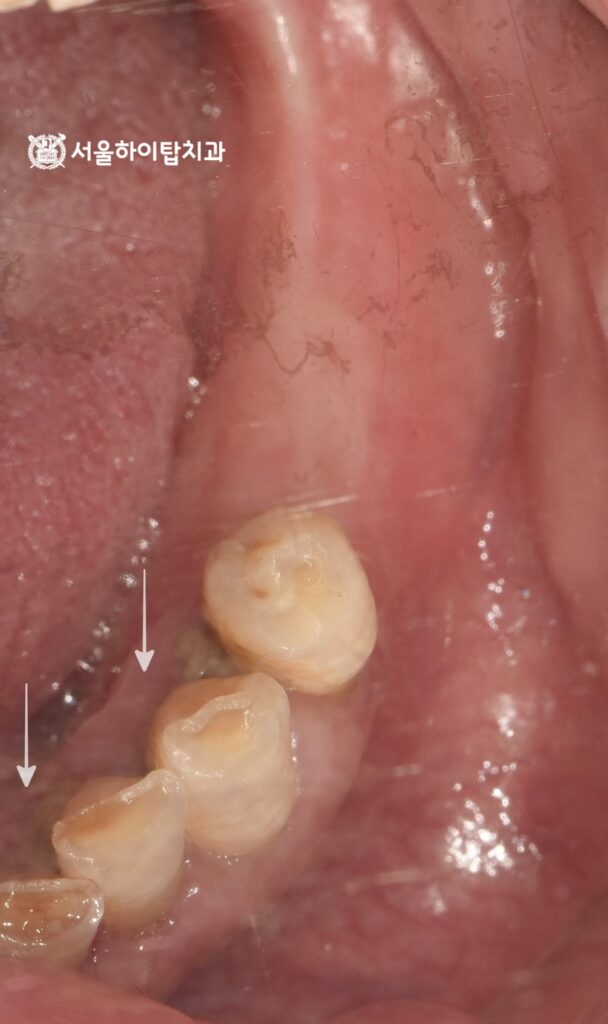

4. 최종 결과

골 융합이 충분히 이루어졌으며,

지르코니아 크라운으로 제작되면서

기능과 심미 모두 만족스러운 결과를

얻은 것으로 보여집니다.

이제는 양쪽 구치부를 활용한

균등한 저작을 할 수 있으며,

앞으로는 꾸준한 구강 관리와 정기검진을 통해

임플란트 주변 조직 건강을 유지하는 것이 중요합니다.